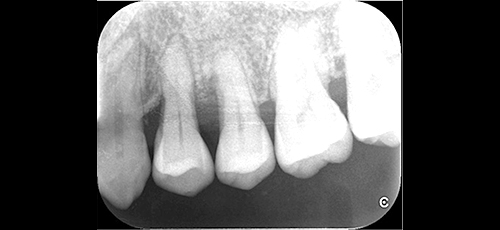

Case.1

治療前